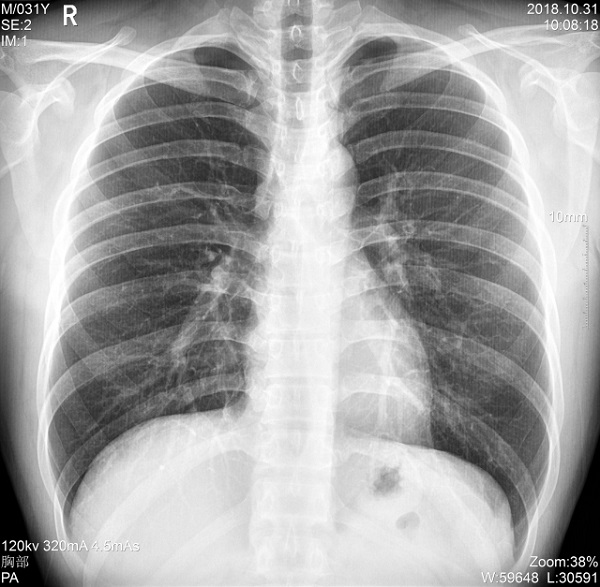

二、1ms 短時曝光 定格心肺運動瞬間影像

PLX5500能夠在最短1ms的曝光時間內輸出足量的X射線,獲取清晰圖像。特別適用于拍攝肺炎、塵肺病、肺結核等難以憋氣的患者,避免了因患者肺部呼吸運動而產生的運動偽影的影響,瞬間定格清晰圖像,以供醫生精確診斷。